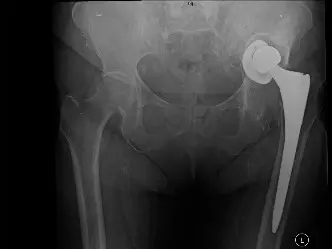

صورة توضيحية لـ ألم مفصل الورك الصناعي: دليل شامل للمرضى من الأسباب إلى العلاج والتعافي مع الأستاذ الدكتور محمد هطيف

رسم توضيحي لمكونات مفصل الورك الصناعي ومحاوره التشريحية